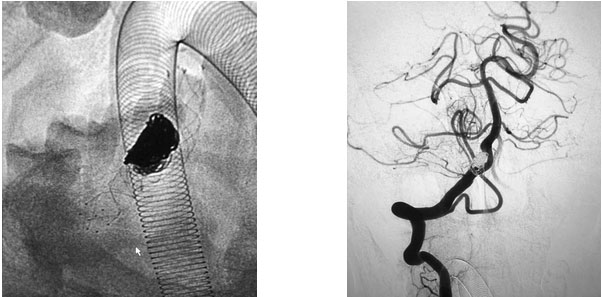

在充分準(zhǔn)備后,張琪博士在劉春醫(yī)生、周林華醫(yī)生協(xié)助下為患者進(jìn)行了支架輔助動(dòng)脈瘤栓塞手術(shù)。填入彈簧圈后,再置入支架,完全釋放后,造影顯示動(dòng)脈瘤無顯影,支架覆蓋良好,載瘤動(dòng)脈通暢,撤出微導(dǎo)管輸送系統(tǒng),復(fù)查雙側(cè)椎動(dòng)脈造影顯示遠(yuǎn)端血流通暢。

▲ 張琪博士正在為患者手術(shù)

▲ 術(shù)后,造影顯示動(dòng)脈瘤無顯影,栓塞成功